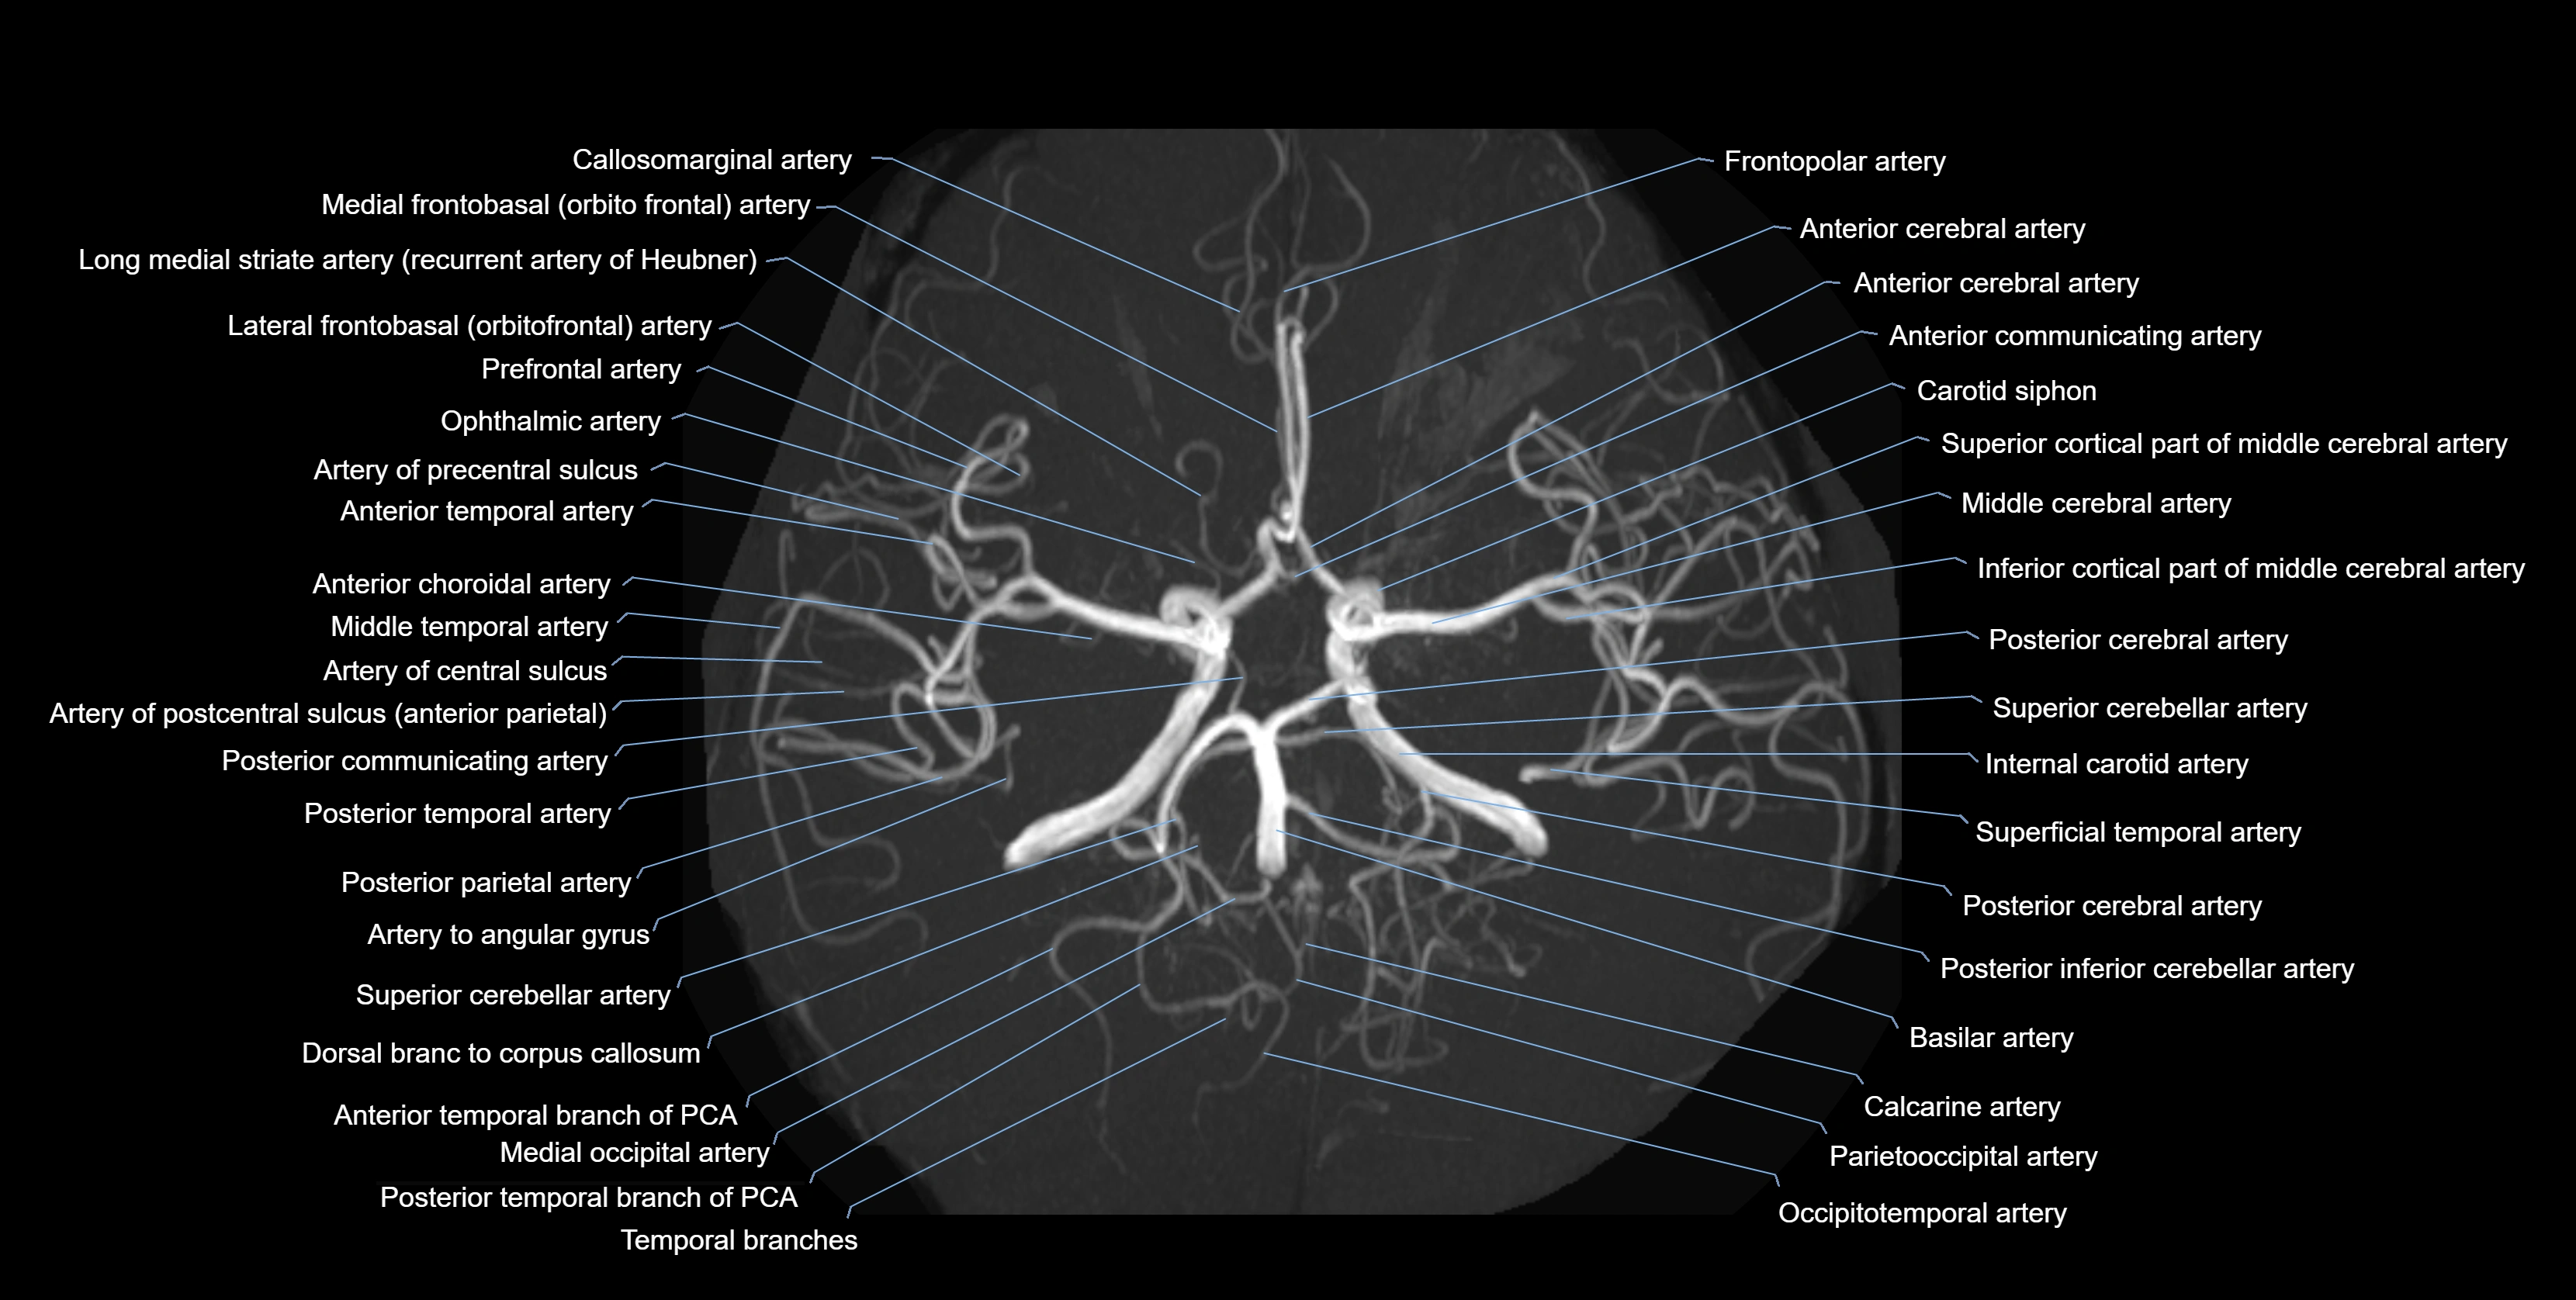

MRI images

image